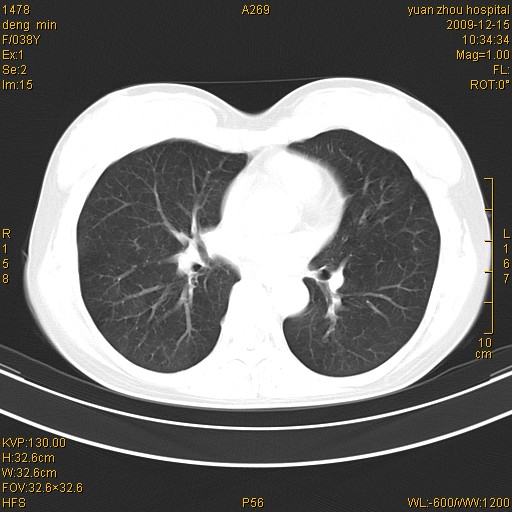

标题: CT23919:F38Y 咳嗽月余 [打印本页]

标题: CT23919:F38Y 咳嗽月余

右肺中下叶、左肺上叶舌段及左肺下叶支气管扩张合并感染。